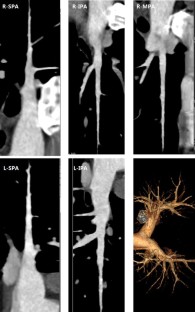

Fig. 3